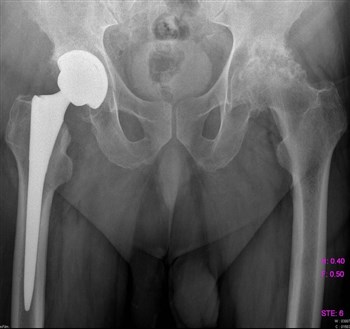

Артроз тазобедренного сустава

Все чаще и чаще пациенты обращаются с жалобами на боли в паху, в колене, иногда на боль в ноге, на скованность движений, нарушение походки.

Как правило, страдают таким недугом женщины после 40 лет.

Боль локализуется в вышеуказанных местах как на одной, так и на обеих ногах.

Если заболевание не в хронической форме, или, проще говоря, не запущено, то лечение происходит обычным парацетамолом, без какого-либо хирургического вмешательства. Лечащий доктор назначает курс массажа, лечебной гимнастики, постоянный контроль ортопеда. При ноющих болях прописывается курс болеутоляющих – Кеторол, Диклофенак.

Немаловажное значение имеет обувь. Она должна быть качественной, лучше ортопедической.

Из-за артроза боли в паху и пояснице чаще всего появляются у женщин в возрасте от 45 лет. Заболеванию могут подвергнуться сразу оба сустава или же один. Определить болезнь непросто, она маскируется под массу других. Первые проявления могут заключаться в том, что «ломит» около ягодиц, а боль возникает при минимальных нагрузках.